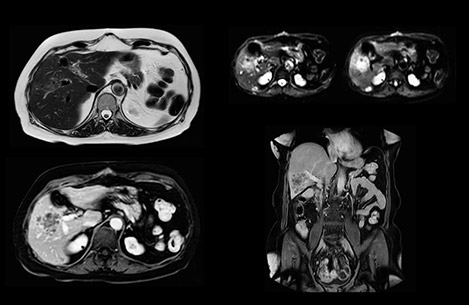

Dr. Baumann then implemented MultiVane XD for motion correction. It uses an extended reconstruction algorithm for imaging that is virtually motion free. “With MultiVane XD we get excellent motion-corrected images with high spatial resolution. We typically first optimize our scan for high image quality, and when satisfied with that, we try to reduce the scan time. So, we combined MultiVane XD with dS SENSE, which allows us to shorten the scan time,” he explains. “The performance of MultiVane XD in liver imaging is outstanding. MultiVane XD with dS SENSE is a powerful development in improving liver image quality.” “As we use breathhold imaging for T2-weighted liver scans, we depend on the patient’s ability to cooperate with the exam. This can present a real challenge when we are looking for small lesions, such as in our oncological patients. However, with MultiVane XD motion correction, we get excellent images. This is important for our surgeons, because they want to know exactly where the lesions are.”

In this example the image quality of the MultiVane XD images is evidently better than in the images without MultiVane XD. Ingenia 1.5T with dS Torso coil solution.

“Our liver exams are quite fast,” says Dr. Baumann. “If the patient tolerates it, we use an arms-up position to reduce the FOV and speed up the exam with dS SENSE.” “We acquire one transversal high resolution T2-weighted sequence with 3 mm slice thickness, for example for pancreas or liver lesions. Then we also add a T2 fat suppressed MultiVane XD SPIR sequence. We perform these two routinely in our liver imaging. We use high dS SENSE factors to significantly shorten scan times to 2-4 minutes, which can improve our protocol; it’s a very robust scan.” “We include mDIXON for the dynamic sequences because of the robust and homogeneous fat suppression we get with that. We had been using eTHRIVE, but we are now quite happy with mDIXON. Sometimes we use a medication to calm the bowels, to further improve the image quality.”

“We are more confident in our diagnosis if we don’t have to rescan the patient and compare it to other studies; this liver exam gives us good image quality in a faster time than the default system’s approach with arms down. That makes a difference for the patients, too. The shorter scan times, especially with the high dS SENSE factors, shorten the duration of the total examination. At the same time it’s more comfortable for the patient, to rest normally without holding the breath, just relaxing.”